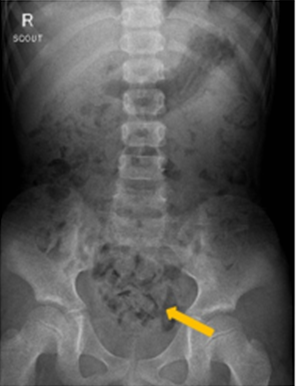

우선 충분한 병력청취와 신체검사가 필요합니다. 요로감염 동반 유무를 확인하기 위한 소변검사, 변비 유무 확인을 위해 복부 X-선검사(그림 2), 소변 속도 및 양, 소변 패턴을 확인할 수 있는 요속검사(그림 3), 배뇨 후 남아있는 소변양을 측정하는 잔뇨검사, 평소 배뇨증상을 확인하기 위해 배뇨일지를 작성합니다. 치료에 반응이 없거나 요로감염 등이 동반되었을 경우에는 초음파나 요역동학검사(또는 비디오요역동학검사(그림 4)) 등을 시행할 수 있습니다.

그림2. 복부 X-선 검사(화살표:대변이 많이 차 있는 모습)